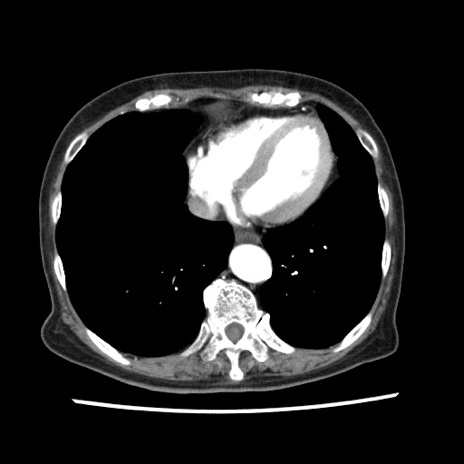

冠状断像

【症例】80歳代女性

【主訴】腹痛

【現病歴】8時間前から腹痛あり来院。

【既往歴】糖尿病、脂質異常症、子宮体癌にて子宮全摘術

【身体所見】意識清明・会話良好だが腹痛で苦悶様、全腹部にわたって反跳痛と圧痛あり

【データ】WBC 13600、CRP 0.14、LDH 224、CK 90